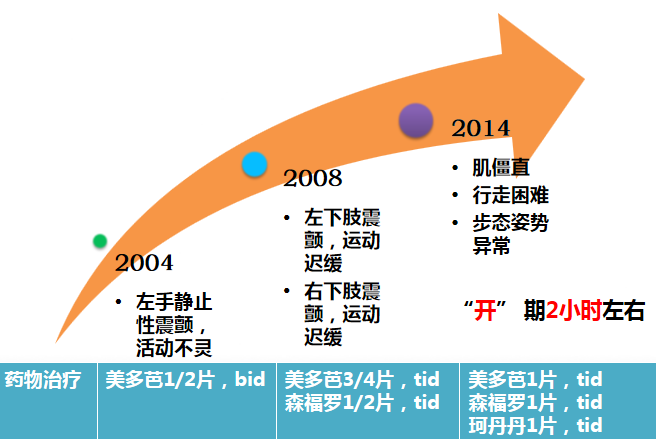

中年女性,52岁。

病程:10余年。

主要临床表现:运动迟缓、静止性震颤、肌僵直、步态姿势异常。

美多芭治疗有效。